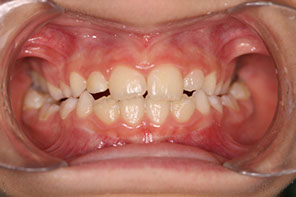

a.- Clase I, ésta es una relación que se establece en la mordida en que los molares superiores están posición de engranaje con los inferiores. Esta es una característica normal, sin embargo se puede combinar con dientes chuecos con falta de espacio u otros.